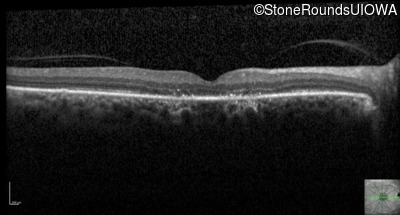

Optical Coherence Tomography - Right - 20/80 -1 sc

Exemplar / OCT Stack